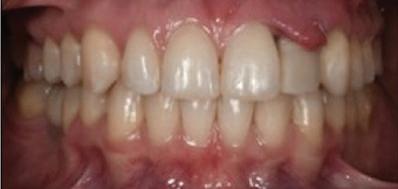

планта бе поставена временна коронка (фиг. 10 и 11), докато бъде изготвена окончателна та. Бе постигнат отличен кра ен резултат. Меките тъка ни около импланта напълно заздравяха, което доприне се за перфектната хармония между бяла и розова естетика (фиг. 12–15).

Dental Tribune Bulgarian Edition / октомври 2022 г.18 воначалния план. Тези пробле ми бяха адресирани чрез допъл нителна поръчка на алайнери с торк контрол и зададено екст рудиране на задните зъби с цел установяване на добри оклузал ни контакти в дисталните об ласти, като бяха предвидени и оптимизирани атачмънти с контрол над корените за корекция на ангулацията на макси ларните резци (фиг. 8). Резултати от лечението Панорамната рентгено графия след ортодонтското лечение показа благоприятна паралелна позиция на съседни те зъби, подходяща за поставя не на имплант в областта на #22, както и конвергенция на ко рените на зъби #44 и 45 (фиг. 9), но преценихме, че няма да от деляме допълнително лечебно време за коригирането ѝ поради факта, че пациентката бе мно го доволна от постигнатия до момента резултат. След при ключване на лечението бяха постигнати отлични взаимо отношения клас I при мола рите и канините, а срединни

съвпадаха. Върху им